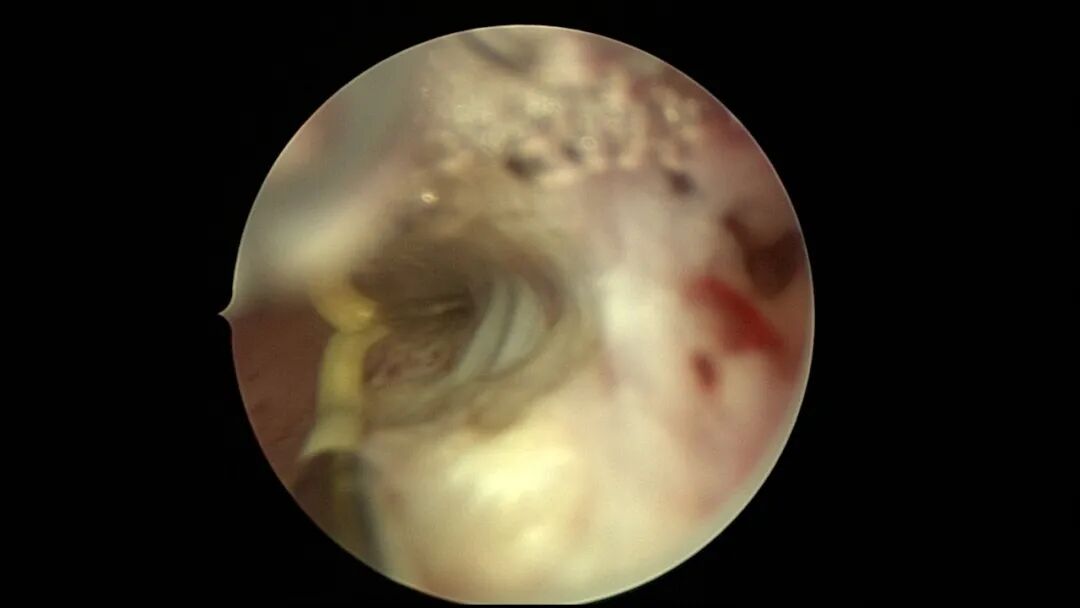

第七次宫腔镜:2025年6月因异常子宫出血、月经淋漓不净10+天,行宫腔镜探查,宫颈管见陈旧血丝,宫腔形态欠规则,宫腔两侧纤维性粘连,宫腔狭小,内膜薄,内膜充血。单极电针分粘,宫腔形态基本恢复正常,左侧输卵管开口显露,右侧输卵管开口不可见。内膜病检为增殖期样子宫内膜伴出血。